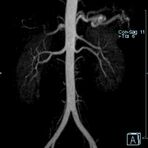

Aorta

• Bauchgefäße

• Erfassung und Verlaufskontrolle bei arteriellen Aneurysmen (Aussackungen der Arterien), vor allem der Bauchaorta

• Darstellung von Gefäßengen an Nierenarterien, Baucharterien und Becken-/Beinarterien

MR-Angiografie (MRA)

Angiographie ohne Kontrastmittel

• MR-Angiografie ohne Kontrastmittel

• Time of Flight (TOF)-Angiographie

• Phasenkontrastangiographie (PCA). Geeignet zur Quantifizierung Stenose-/Insuffizienzgrad z.B. bei Herzklappen, falls echokardiographisch die Untersuchungsbedingungen eingeschränkt sind.

Je nach Fragestellung und Körperregion Gefäßdarstellung ohne Kontrastmittel bei Kontrastmittelunverträglichkeit oder terminaler Niereninsuffizienz möglich.

Ganzkörper Angiographie mit Kontrastmittel

• MR-Angiographie mit Kontrastmittel

• Erfassung arterieller und venöser Gefäße/Bypässe aller Körperregionen mit 3D-Rekonstruktion

• je nach klinischer Fragestellung zeitaufgelöste MR-Angiographie (4D-MRA) z.B. bei Frage arteriovenöse Fistel/ Shunt oder Darstellung Unterschenkelarterien vor geplanter Bypassoperation.